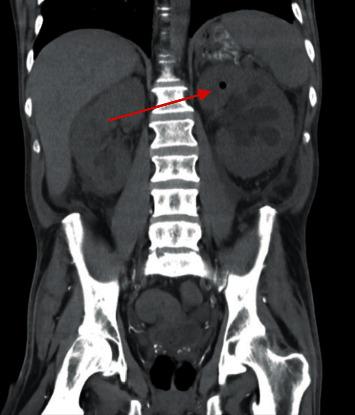

Fungemia due to obstructive urinary tract fungal ball is exceedingly rare. These patients often have multiple predisposing conditions, including diabetes or antimicrobial exposure. While candiduria can be relatively common in this population, urinary tract fungal balls are a rare entity. Hospitalists should be aware of this rare complication in patients presenting with funguria. . We present a case of a 44-year-old male with type II diabetes, chronic hepatitis C secondary to injection drug use, and chronic kidney disease who developed a urinary tract fungal ball leading to fungemia and subsequent bilateral chorioretinitis, additionally complicated by emphysematous cystitis and pyelonephritis. Additional invasive treatment options beyond typical antifungals are often required in the case of urinary tract fungal ball, and in this case, bilateral nephrostomy tubes and micafungin were employed. Hospital course was complicated by fungemia with subsequent bilateral fungal chorioretinitis on dilated fundus exam. This was effectively treated with cyclogyl and prednisolone drops along with bilateral voriconazole injections. Follow-up imaging and cultures showed resolution of fungemia, urinary tract masses, and chorioretinal infiltrates; however, recurrent polymicrobial UTIs continue to be an issue for this patient.

梗阻性尿路真菌球引起的真菌血症极为罕见。这些患者通常有多种易感因素,包括糖尿病或抗菌药物暴露。虽然念珠菌尿在该人群中可能相对常见,但尿路真菌球是一种罕见的病症。住院医生应意识到在出现真菌尿的患者中存在这种罕见并发症。我们报告一例44岁男性患者,患有II型糖尿病、因注射吸毒继发慢性丙型肝炎和慢性肾脏病,他发生了尿路真菌球,导致真菌血症及随后的双侧脉络膜视网膜炎,此外还并发气肿性膀胱炎和肾盂肾炎。对于尿路真菌球病例,通常需要除典型抗真菌药物之外的其他侵入性治疗选择,在本病例中,采用了双侧肾造瘘管和米卡芬净。住院期间病情因真菌血症而复杂化,散瞳眼底检查发现随后出现双侧真菌性脉络膜视网膜炎。使用环喷托酯和泼尼松龙滴眼液以及双侧伏立康唑注射有效地治疗了该病。随访影像学检查和培养显示真菌血症、尿路肿块和脉络膜视网膜浸润消退;然而,复发性多种微生物尿路感染仍是该患者的一个问题。